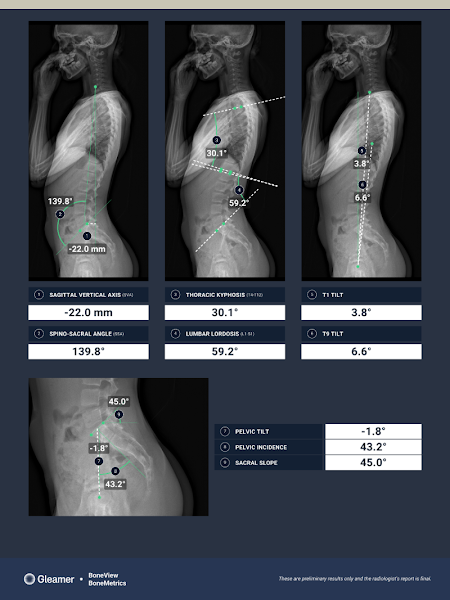

Convinced that AI raises quality standards in the healthcare field while contributing to increased reliability in diagnoses, Gleamer is pursuing a two-pronged expansion strategy. On the one hand, the company is expanding its catalog to cover all imaging modalities. After establishing its expertise in standard radiology with several certified products, the company is deploying its new medical devices for mammography and CT scans, with MRI as the next step.

In fact, the clinical performance of Gleamer's solutions demonstrates the transformative impact of AI in radiology. Validated by over 30 scientific publications, they show an average improvement of 30% in lesion detection, allowing general radiologists to reach the level of specialists. And unlike human expertise, which can falter during night shifts or after long hours, AI maintains this constant level of excellence, guaranteeing optimal diagnostic quality 24/7.